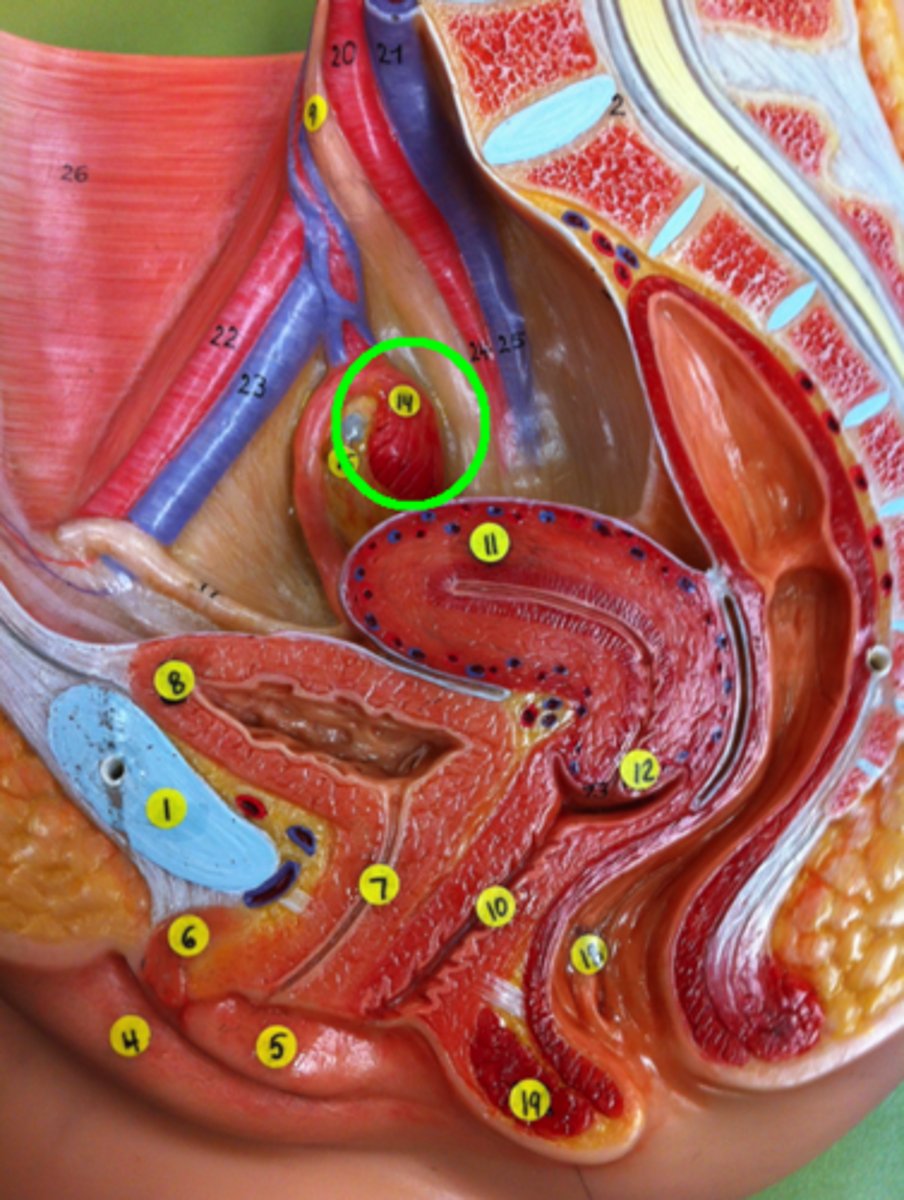

Fimbriae of Uterine Tube